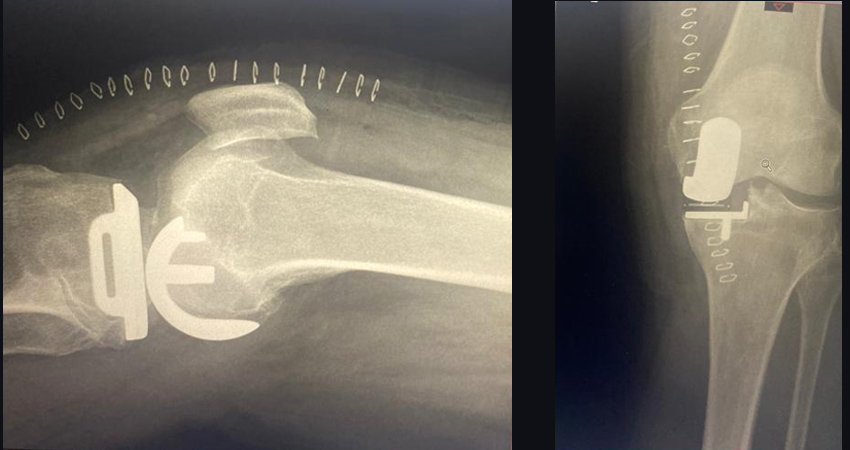

Partial Knee Replacement